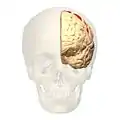

Brodmann area 4 (orange) | |

Image

Animation.

Animation. front view.

front view. Lateral view.

Lateral view. Medial view.

Medial view. Lateral surface.

Lateral surface.